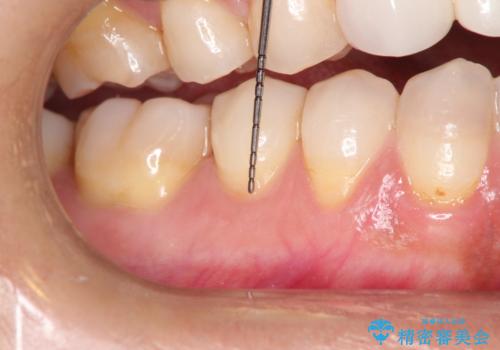

- 昔に受けた矯正治療がきっかけで歯肉が下がってしまった事を主訴として来院された患者様です。

結合組織移植術を行う方法を提案しましたが、傷口が口蓋にもできるのが嫌だとのことで、代替案としてバイオマテリアルを併用した根面被覆術を計画致しました。

治療対象部位は右下4,5,6番の3本です。